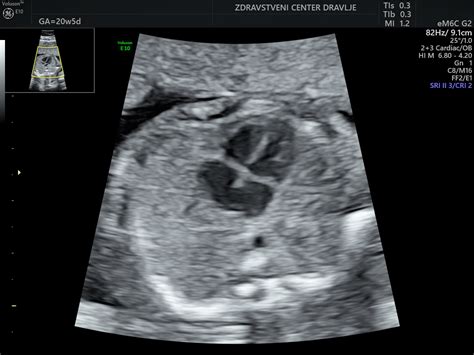

Dvajseti Teden: Morfologija in Polovica Nosečnosti

Dvajsettedenski plod meri 19,7 cm in tehta 260 gramov. Notranji organi so že na svojem mestu kot pri odraslem. Okoli 20. tedna se opravi obširnejši ultrazvok, imenovan morfologija, ki pregleda razvoj posteljice in otroka ter pogosto omogoči določitev spola. Nosečnica je presegla polovico nosečnosti.